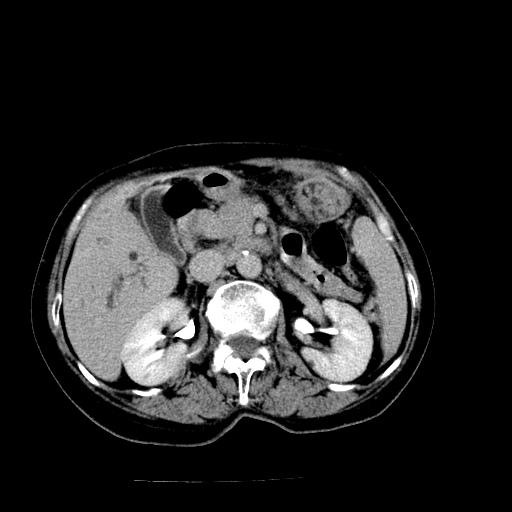

以下是引用随光逐影在2009-4-7 8:21:00的发言:[br]肝内外胆管多发性结石并肝内外胆管扩张;胆系感染。